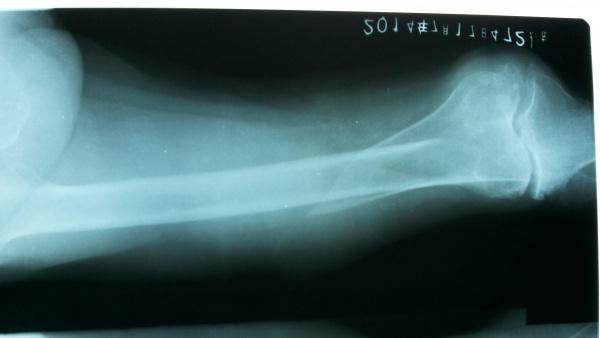

90岁股骨远端长螺旋形骨折

现病史:患者于1+小时前,在走路时不慎跌倒,左大腿部着地受伤,当时无昏迷、无呕吐、无抽搐及二便失禁,伤后感大腿部疼痛、活动受限,在外未经任何特殊处理,急来我院。X摄片示:左股骨远端螺旋形骨折,胸片、骨盆未见外伤性改变。

辅助检查:X片示:左股骨远端螺旋形骨折,胸片、骨盆未见外伤性改变,左膝关节退行性改变

初步诊断:1、左股骨远端螺旋形骨折 2、左胸壁挫伤 3、美尼尔氏综合症 4、双肾结石症5、左膝骨关节炎

3、术前、术中、术后特别需要注意的问题? 入院时正侧位

入院时侧位

入院时正位